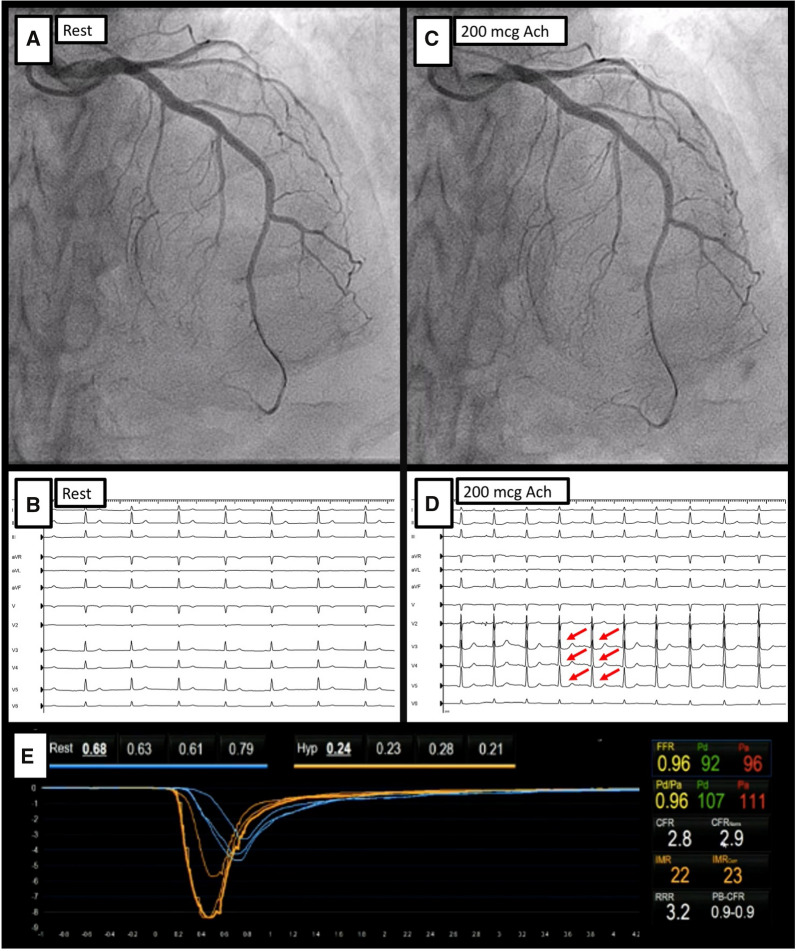

Acetylcholine testing. Figure demonstrating the invasive physiological assessment of CMD and vasomotor disorders in a 65-year-old female, with repeated episodes of angina at rest. Coronary angiography identified no obstructive CAD. In Panel A and Panel B, baseline coronary angiography shows the wire advanced into the distal LAD and a resting ECG without repolarization abnormalities. Following the infusion of intracoronary acetylcholine (up to 200 mcg, Panel C and Panel D), the patient described chest pain with similar characteristics to her previous episodes, supported by an ECG with pronounced ST-segment depression in the anterior leads. Coronary angiography showed an absence of epicardial coronary spasm. After the infusion of intravenous adenosine, CFR and IMR were calculated, with normal values (Panel E). A final diagnosis of microvascular spasm was established